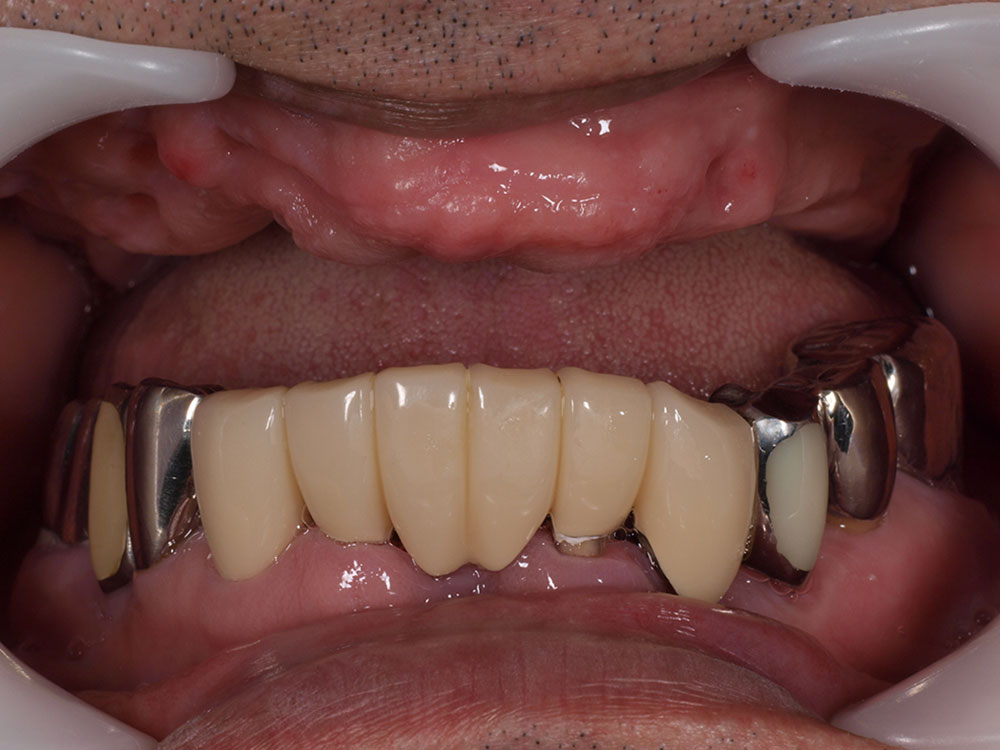

症例紹介

- 主訴

- 入れ歯が合わない。食べにくい。人生を豊かにしたい。

- 処置内容

- 上顎4本で12歯(オールオン4)、下顎4本5歯。

上下抜歯即時埋入、即時荷重(手術当日にインプラントの上に仮歯装着)

- 治療費用

- 上顎:約290万(税込)、下顎:約210万円(税込)

- 治療期間・通院回数

- 上顎:9か月/9回

下顎:6か月/7回

- リスク

- 術後の腫れ、痛み(ピークは3日後、1週間で軽減)

上部構造物、仮歯の破折、人工歯根脱落リスクがあります